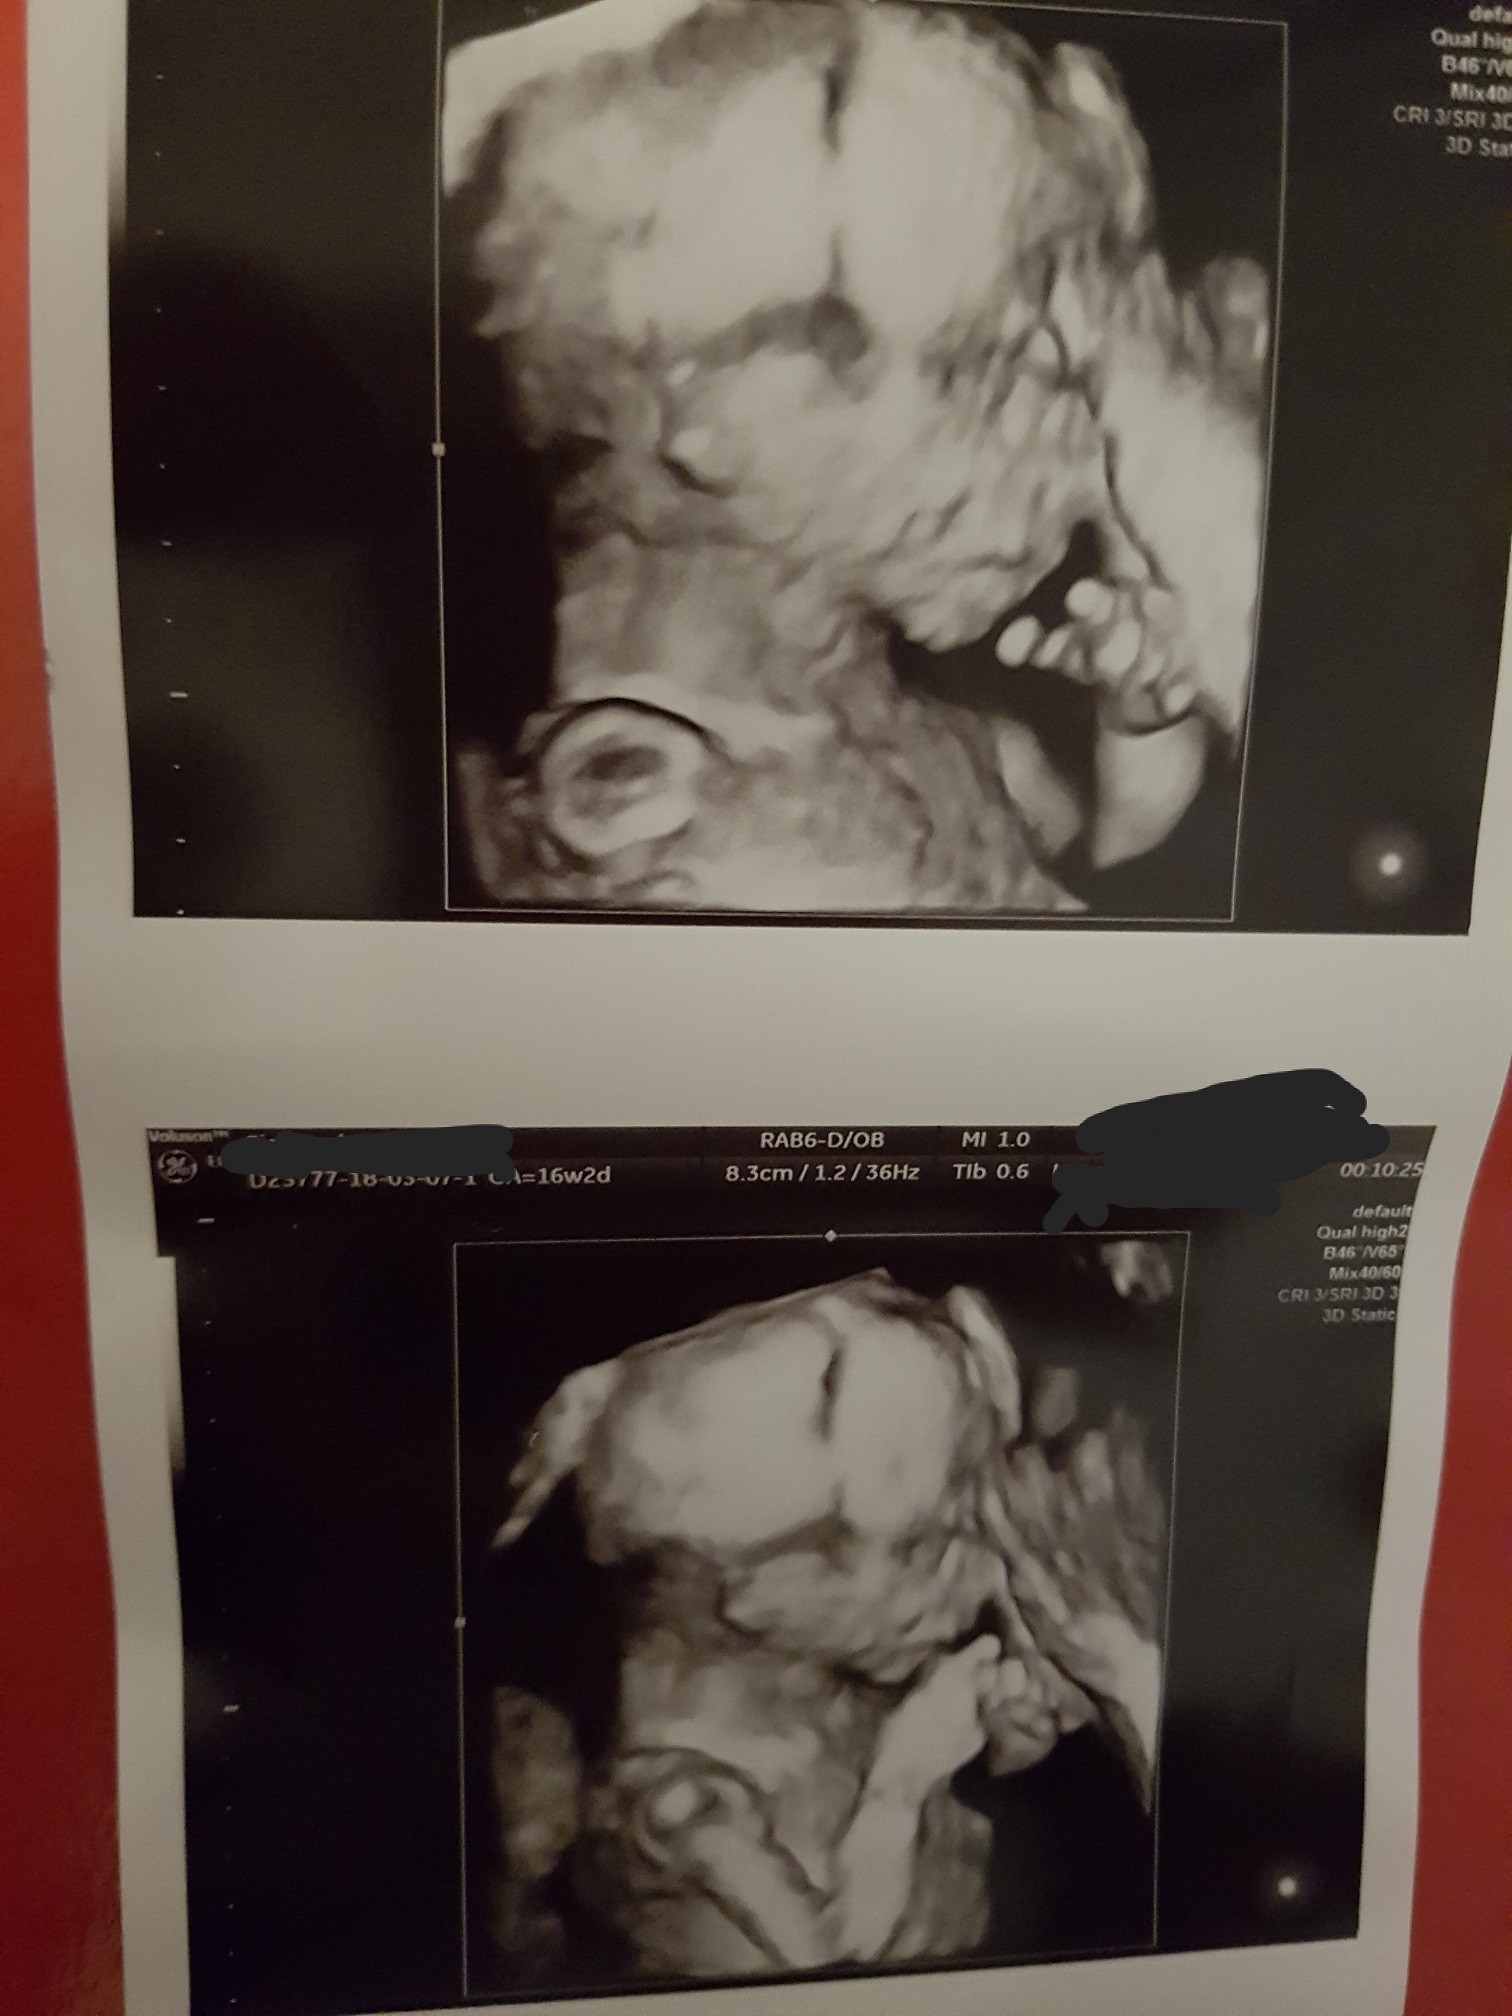

A więc tak .. na wyniki czekamy cały czas.. Po odebraniu Pappy byłam bardzo załamana ,dużo płakałam i w weekend zaczęłam się martwić o mojego dzidziusia.. Postanowiłam ,że napisze do mojego ginekologa do którego się zgłosiłam z naszym problemem (skierował mnie na laparoskopie , pozniej podchodziłam tam do IUI) ..przyjął mnie wczoraj bez żadnego problemu ,żeby sprawdzić czy wszystko z nami dobrze. Poświęcił nam bardzo dużo czasu,rozmawialismy o ivf ,o wynikach Pappy, zbadał mnie dokładnie a pózniej zrobił USG ,które trwało z 15 minut albo i dłużej.. mierzył naszego maluszka , patrzył kość nosową i cały czas mówił,że z naszą kruszynką jest wszystko dobrze i nie ma innej opcji żeby wyniki NIFTY wyszły zle. Wszystko pokazywał i omawiał . Uspokoiłam się. Na koniec powiedział ,że bardzo się cieszy,że nam się udało i trzyma kciuki bo innej opcji nie widzi jak tylko to ,że musi być dobrze bo nic nie wskazuję na to ,że może być inaczej!

Zamieszczam zdjęcie mojego okruszka ! 159 gram szczęścia ! :)